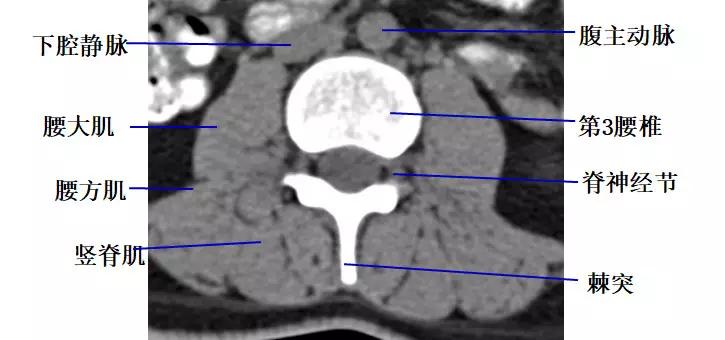

腰段横断面解剖及影像

1.经腰椎椎弓根的横断层面(CT)

2.经腰椎椎体下部的横断层面(CT)

3.经腰椎椎间盘的横断层面(CT)